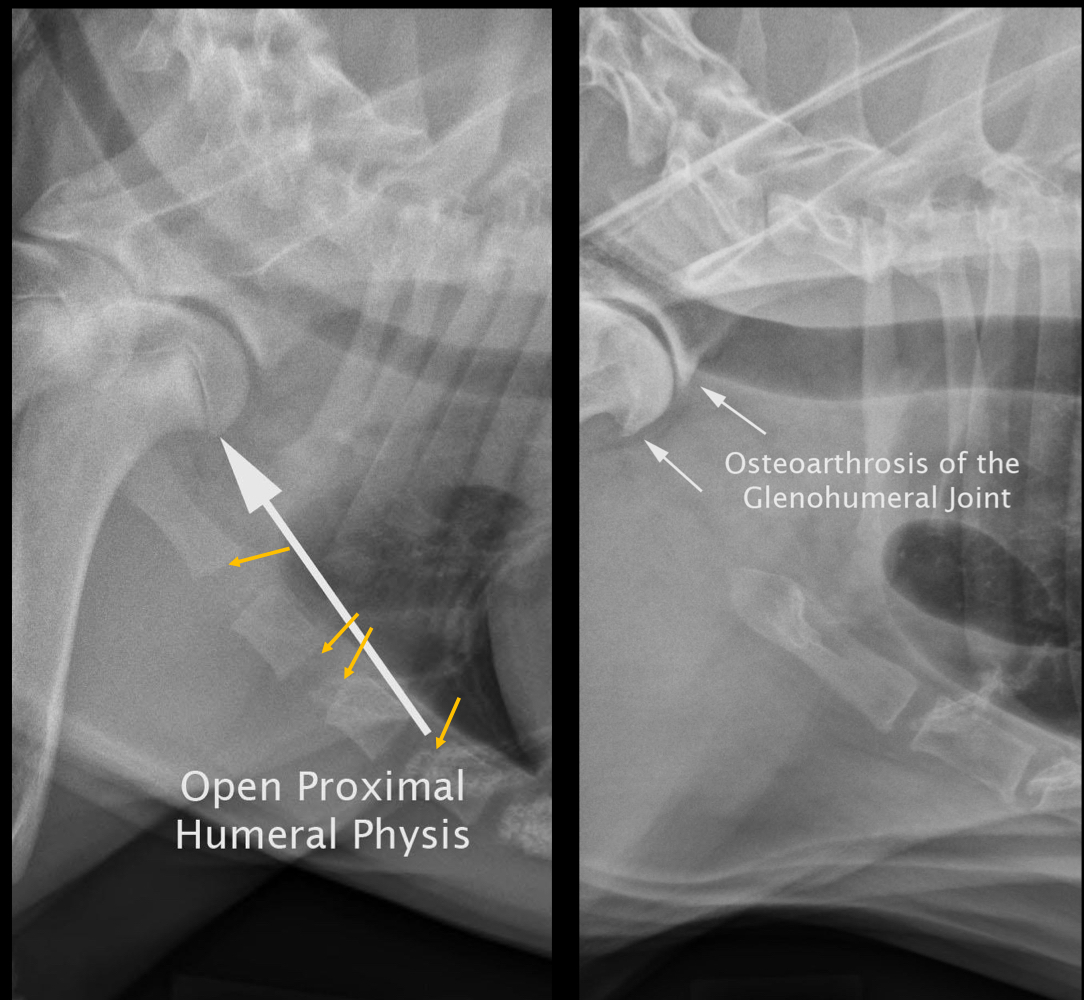

Thoracic limbs of thoracic radiographs:

A

• normal cartilaginous growth of physis at proximal humerus

• periarticular osteophyte proliferation at glenohumeral joint and sternebrae